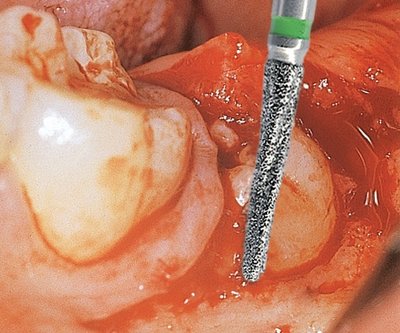

Edenta GSD1 - chirurgické diamantové nástroje, Osteotom - 3 ks